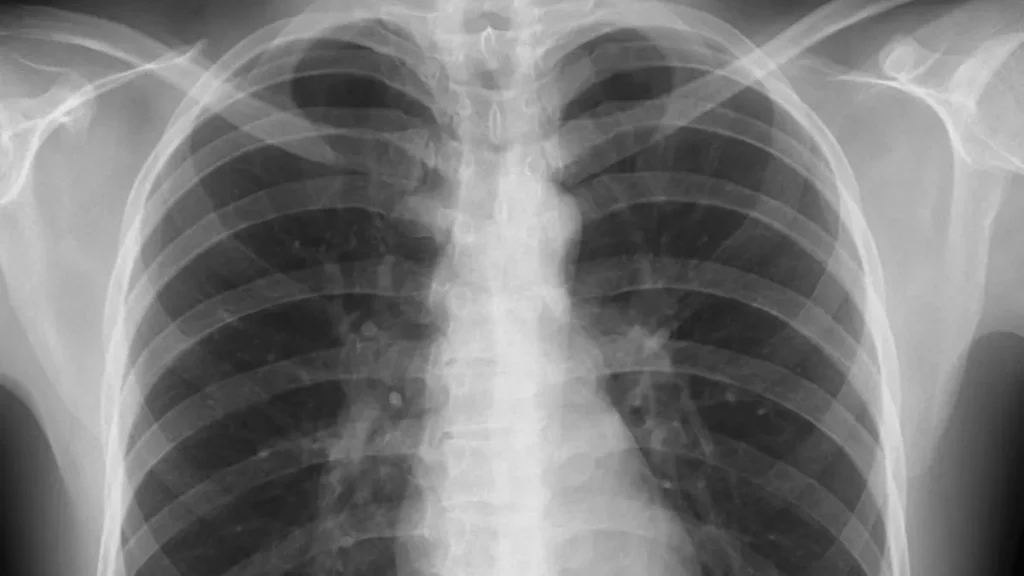

Trained to see patterns by analyzing thousands of chest X-rays, a computer program predicted with up to 80 percent accuracy which patients with COVID-19 would develop life-threatening complications within 4 days, a new study finds.